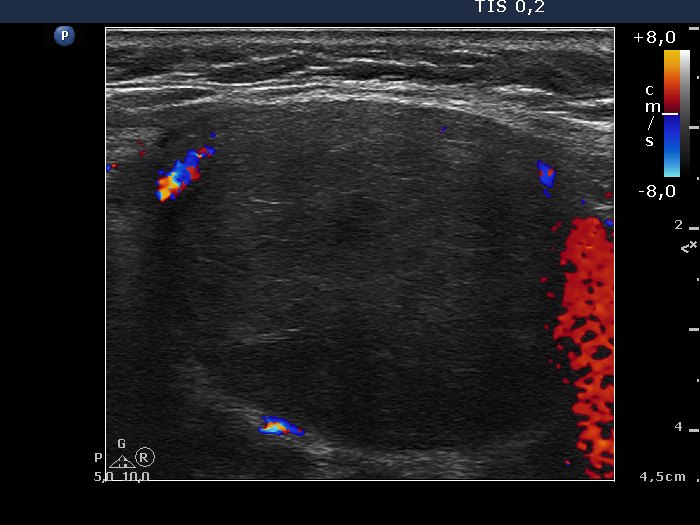

Lymph nodes - case conp 007 (ultrasonographic picture 4)

Right lobe, longitudinal scan, color Doppler mode.